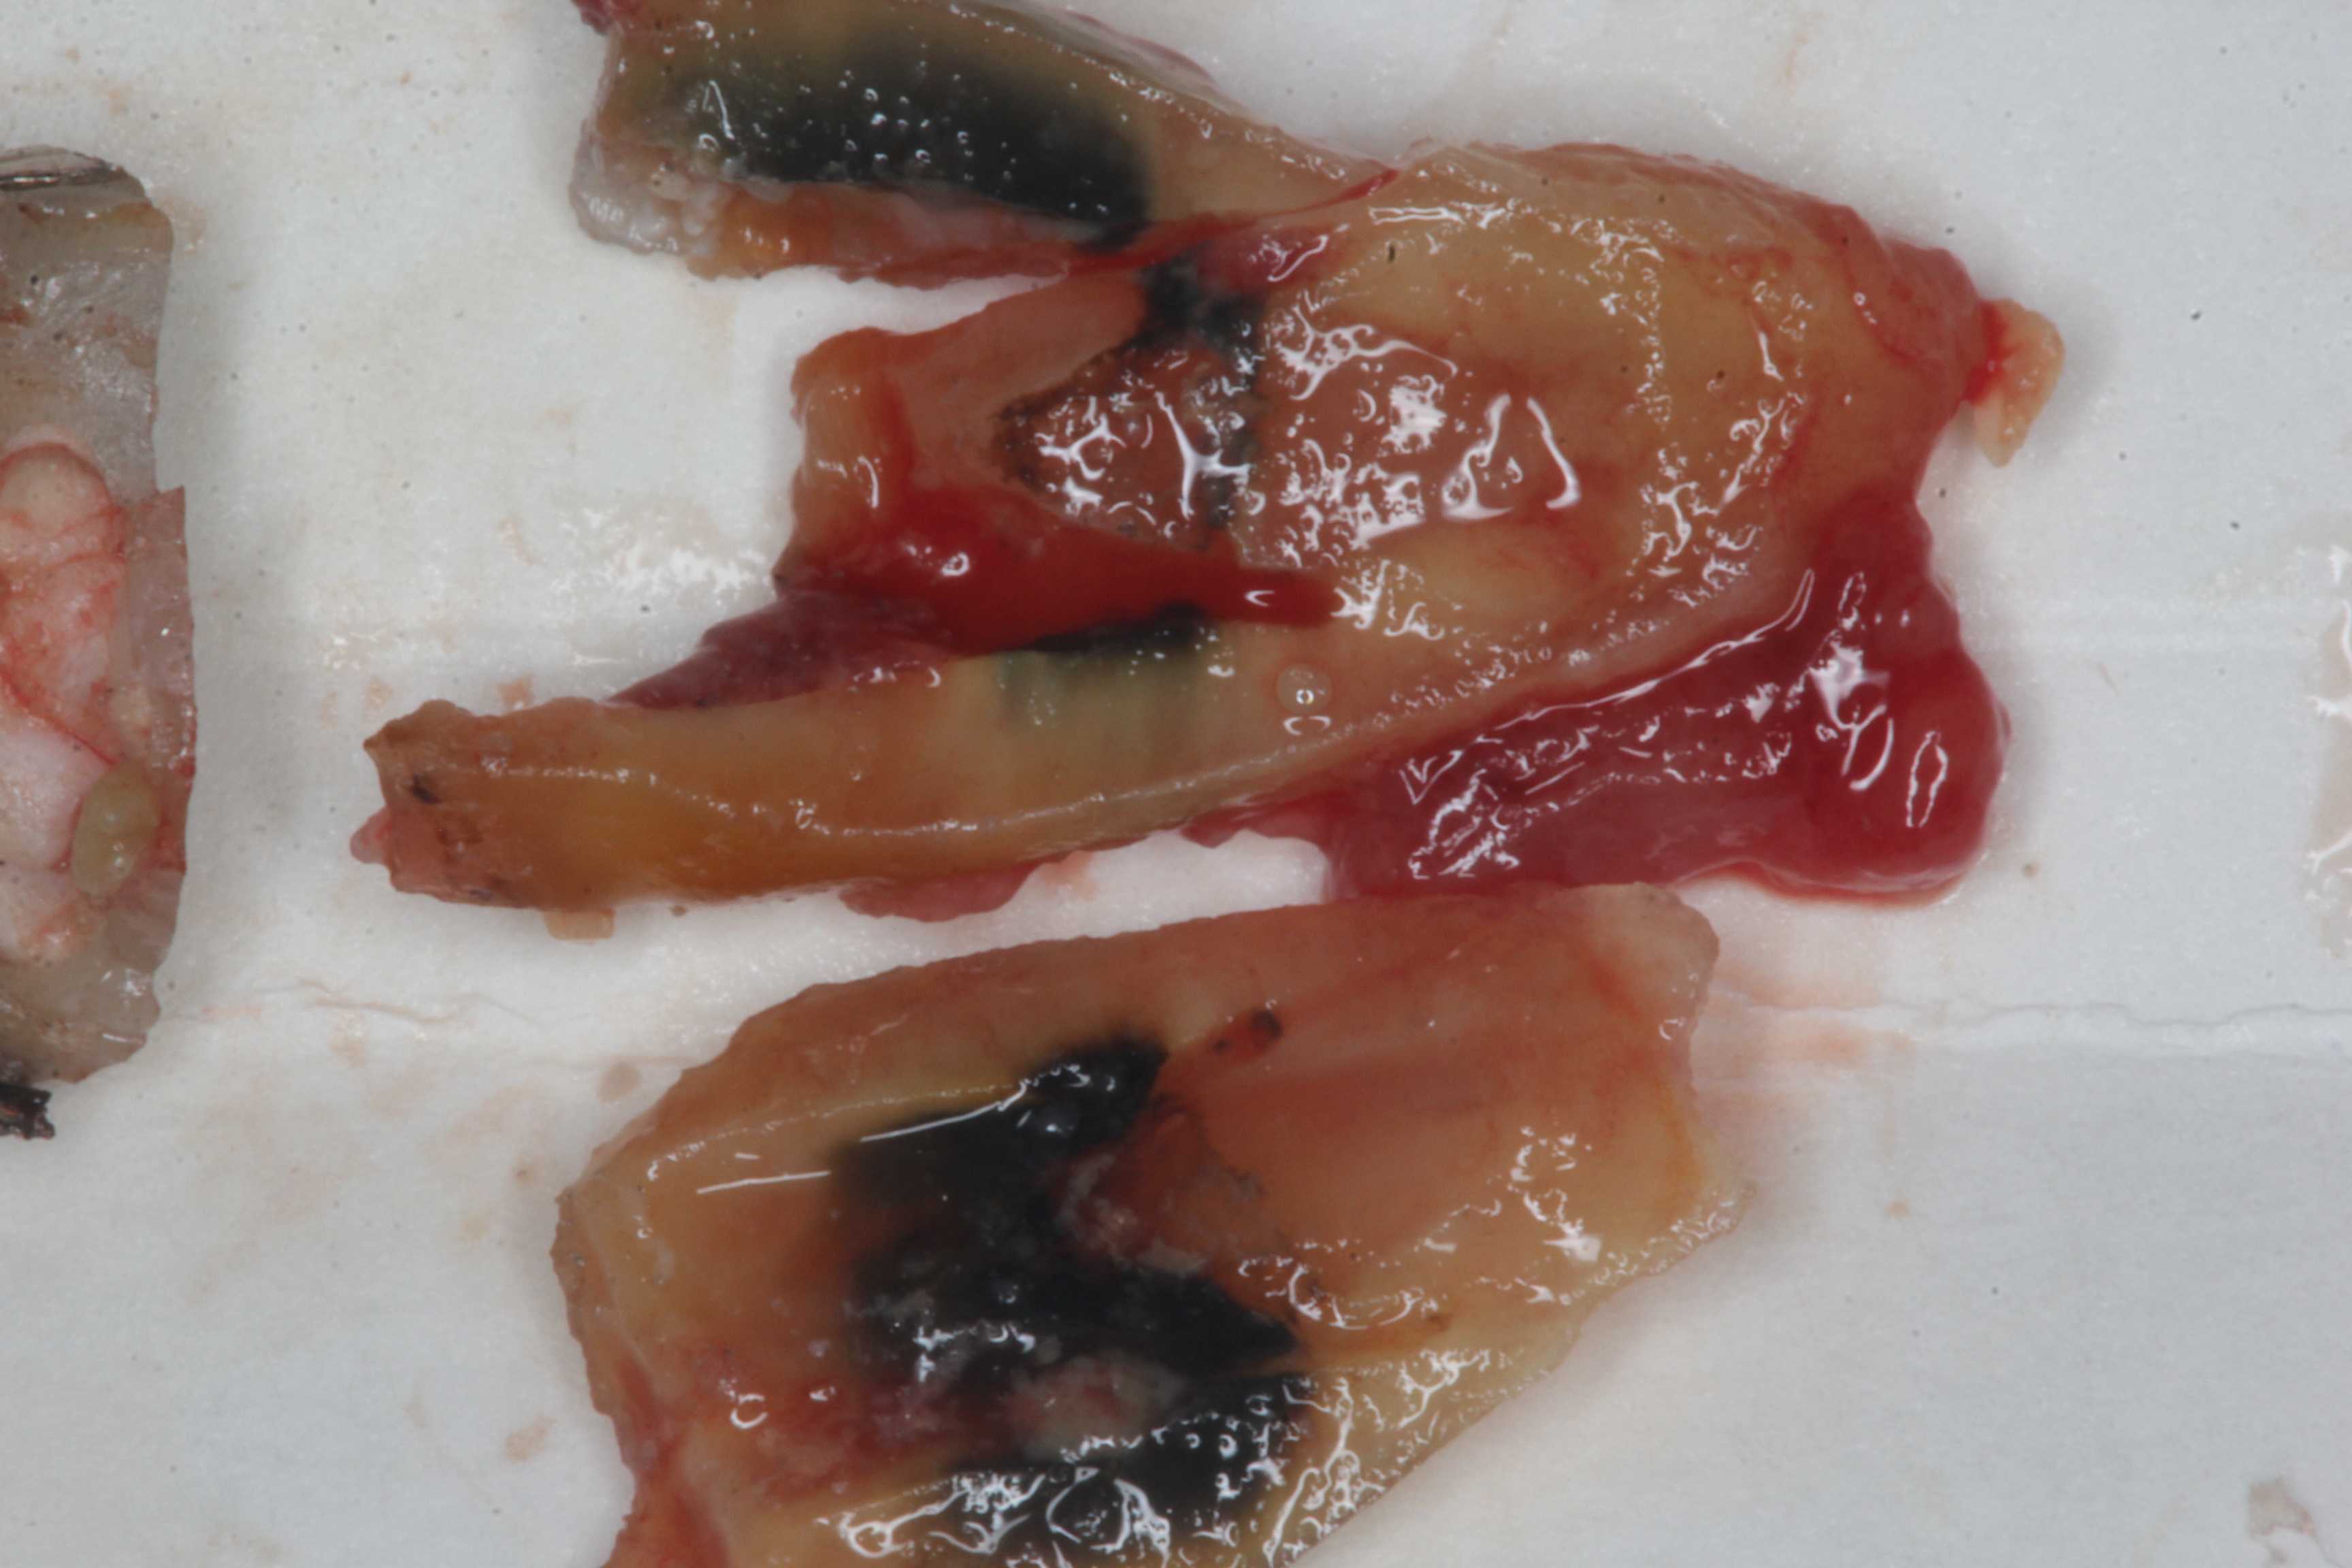

今日の抜歯再植術シリーズ1.2.1

50代女性、左下6、歯根破折前回のつづきhttps://plaza.rakuten.co.jp/mabo400dc/diary/202106250000/歯科医療が患者目線ではなく、既存の歯科治療法に固執し続けている理由は経済的、体力的問題だけではないと思う。歯科医学にはいくつもの誤認、思い込み、オカルト的発想などおよそ科学的ではない認識に溢れている。洗脳と言っても良いかもしれない。歯科医学の基本的な考え方は100年以上も変わっていない。使用する材料や治療法は進歩してはいるが、やっていることは変わらない。虫歯は(歯周病も?)治らないので、何度も修復して、歯根がダメになったら、抜歯して欠損補綴する。これ以外にはない。そもそも虫歯の原因すら誤解されているが、異論を唱える歯科医師がいない。一般にはパスツール的な発想による「虫歯は細菌感染症」と言われているが全くの誤認だ。ここでは虫歯とは電気化学的な腐食『虫歯の電気化学説」ということを提唱しているが、こう考えるとフッ素応用とか歯磨きの徹底とか、訳も分からず盲目的にやっていることの理由も優先順位もわかるし、もっと効果の高い予防法もあることがわかる。それだけではない、虫歯は治るということもわかる。少なくとも安易な修復治療を繰り返したあげく、歯が無くなるという患者にとっては最悪の事態は避けられる、もしくは先延ばしすることができる。歯科医師にとっては飯のタネが減るということなので、認めることは容易ではないと思うが。歯科医師の皆さんそろそろ洗脳を解きませんか?歯科医師が無理なら、一般人から洗脳から逃れませんか?「歯を失う原因は科学的ではない的外れな歯科治療にある。」・・・今日は抜歯から再植までの全ての画像供覧だが、再建部分はほとんど省略してリアルな抜歯と再植過程を強調する。再建過程は見ていてもよく分からないと思うからだ。では時系列でどうぞ

今日の抜歯再植術シリーズ1.2

50代女性、左下6、歯根破折ここのコメント欄にもあるように、患者目線でのきちんとした治療ができない理由だが、この100年以上にわたって強固な診療システムが確立していて、このシステムから逸脱することが非常に困難だからだと思う。歯科医療は分業体制で成り立っており、ま、どこの世界でも同じではあるが、例えば、よくある治療の流れは1、神経を取って型取りする2、歯科技工士に冠の作製を依頼する3、納品された冠を口腔内にセットするだが、この流れからドロップアウトするといきなり経済的に、もしくは肉体的に行き詰る。僕は歯科技工士上がりなので、1から3まで全部できはするが、実際にやると寝る時間が無くなり、倒れる。2年は頑張ったが。では無理のない範囲でゆっくりやれば良いではないかと思われるかもしれないが、それでは食べていけないだけではなく、患者をさばけない。患者単価が非常に高くなってしまうからだ。では、僕はどうなのかといえば?歯を削ると問題が生じるのだから、削らない。これは守っている。この症例も安易に削って被せたばかりに問題が生じたと言えるわけなのだが、削らないとすれば、どうやって食べていくか、このブログ記事がその答えでもあるのだ。しかし現実は厳しい。この世は修行だと思って、とことんがんばるしかないと思わないとやっていけないだろう。しかも超絶技巧が必要だ。そんな歯科医師がいるのか?と言われるといるわけがない。誰でも楽をしたい、しかしお金だけは欲しい。今だけ、金だけ、自分だけだ。読者の皆さんはそうではないですか?・・今日はレントゲン写真を3つ挙げておこう。破折した直後。破折線が明瞭に見えると思う。その3ヶ月後、歯根はバラバラになっている。抜歯再植後つづく

今日の抜歯再植術シリーズ1.1

60代男性、左下7、歯根破折あっちのブログはまだ復旧できそうもないので、こっちが続きます。この方、よく噛んで食べると健康を維持できるというお考えの方ではないかと思う。ま、確かにそうなんだが、60も過ぎると歯の耐用年数が来てしまう。歯の機械強度が落ちてくる。歯は劣化する一方なのだ。特に神経を取ってある歯は弱い。最初から神経を取らないようにするべきなんだが、そうではなくても人生100年を見据えるのなら、歯には過度な力をかけずに大切に使うべきだ。近心根は砕けていて使えるパーツが少ない。遠心根にもクラックが入っていて離断寸前だった。さすがに再建しても生着は厳しいかと思ったが、諦めないでやってみようと思った。歯根表面の40%近くが◯ーパー◯ンドになってしまったが、その上にもセメント質も歯根膜も再生することもある。確か猿での実験で確認されたという論文を見たことがある。人間でも当然あると思う。ただ、強固な歯牙固定が必要になるが、隣在歯にはセラミックインレーが入っており、接着が強固にはできないのが問題だ。最初はレントゲン写真でのbefore/afterだが、さすがに厳しいと思うだろう。beforeafterでは時系列でどうぞ